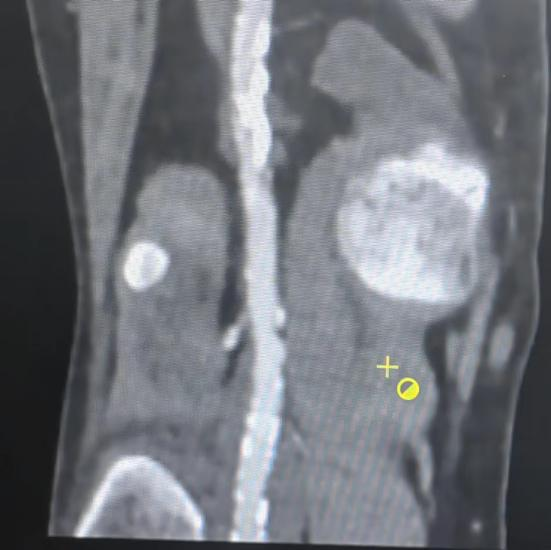

图1:术前下肢动脉CTA检查

今年59岁的朱先生(化名)因“活动后下肢无力、疼痛5月余,进行性加重7天”就诊于当地医院,行B超检查后提示:下肢动脉硬化闭塞症,为求进一步诊治,经多方咨询后前来西安交大一附院榆林医院就诊。入院后,介入血管外科迅速为患者完善术前相关检查化验,CTA检查发现患者双下肢动脉粥样硬化并严重钙化,右下肢腘动脉钙化闭塞。入院诊断:下肢动脉硬化闭塞症;尿毒症透析状态;冠状动脉粥样硬化性心脏病;2型糖尿病。每周血液透析治疗2-3次。就诊时患肢已经出现疼痛、冰凉、麻木、苍白,尤其是夜间静息痛明显,导致患者寝食难安,精神萎靡。“5个月前,我发现自己平地步行200米即出现右腿没劲儿,休息后才能再次行走,但是也走不利索。后来这个症状就一天比一天严重,7天前开始,右腿疼的厉害,实在是疼的受不了了。听说我的血管已经钙化的像钢管一样,不知道还能不能打通。”朱先生焦虑的说。